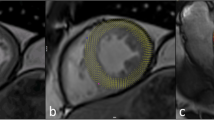

Myocardial function is typically evaluated using cine balanced steady-state free precession (bSSFP) imaging, providing optimal contrast between the blood pool (bright signal) and myocardium (intermediate-low signal). Cine MRI is used to assess ventricular function and valvular function in various orientations (transverse, angulated). As a starting point, the transverse cine images provide a global impression on left ventricular function, regional function (scar, aneurysm), and valvular function (stenosis jet, regurgitation jet, valve morphology). Short-axis cine images are routinely applied for calculation of ventricular volumes (ejection fraction is very important for clinical decision-making and prognostication). LGE-MRI is the reference standard for imaging myocardial scar. Based on inversion recovery methods, contrast is created between normal (dark, gadolinium excluded from intact cells) myocardium and scar (white due to gadolinium accumulation). Both acute and chronic infarct may display LGE. Acute infarcts show LGE due to cell membrane breakdown, whereas chronic collagen scar has little cellular volume and larger volume of distribution and therefore accumulates gadolinium. A particular strength of LGE is visualization of very small scars as well as the transmural extent of necrosis (starts at the subendocardium and may progress through the ventricular wall as a wave front with longer durations of coronary occlusion). Myocardial signal intensity depends on the T1, T2, T2*, and proton density of the tissue. All these parameters are actively explored for better characterizing the severity of myocardial injury. Quantitative maps of myocardial T1, T2, T2*, and extracellular volume (ECV) are attractive alternative methods for better tissue characterization. Quantitative methods for characterizing myocardial tissue based on parametric mapping of T1 and T2 have been explored as an objective tool of detecting and quantifying focal as well as global myocardial tissue alterations. In combination with extracellular contrast agent (gadolinium) injection, T1 mapping can also estimate the extracellular volume (ECV) fraction. Non-contrast enhanced, native T1 mapping and ECV mapping are explored as a diagnostic tool in both acute and chronic myocardial infarction and may be used to assess the area at risk (edema). Many other disease processes in the myocardium may result in elevated (e.g., myocarditis, amyloidosis) or decreased (e.g., Fabry disease, high iron content) native T1 values. Native T2 mapping can detect edema in myocarditis, area at risk, and acute myocardial infarction. Technical details of pulse sequences, acquisition protocols, scanner adjustments, artifacts, image processing (windowing) and other confounders are affecting and complicating reliable determination of parametric maps. Well-controlled and optimized techniques are crucial to improve accuracy (saturation methods), precision (inversion methods), and reproducibility of the use of parametric imaging. The acquisition technique combines an inversion or saturation pulse to pertubate T1, sampling of the relaxation curve, and a model to fit the sampled curve and extract the myocardial T1 value. Initial methods for pixelwise parametric T1 mapping are MOLLI and shMOLLI (modified Look-Locker inversion and shortened breath-hold modified Look-Locker inversion, respectively) sequences. Inversion methods (e.g., MOLLI, shMOLLI), saturation methods (e.g., SASHA, saturation recovery single-shot acquisition), and combined inversion and saturation methods (e.g., SAPPHIRE, saturation pulse prepared heart-rate-independent inversion recovery) are explored to optimize the reliability of acquisition schemes. Motion artifacts have been reduced by schemes that allow high-resolution imaging at the same cardiac and respiratory phase. The ECV in the myocardium is estimated from the concentration of extracellular contrast agent in the myocardium relative to the blood in a dynamic state. The formula for calculation of ECV incorporates hematocrit (determined for each individual from blood sample or synthetic Ht, reflecting blood volume of distribution) and change in relaxation rate between precontrast and postcontrast (proportional to gadolinium concentration, 15 min after bolus injection). Quantitative T2 mapping is commonly performed using single-shot T2-prepared SSFP approach, although other approaches are available. For example, images may be acquired at three echo times, and after monoexponential curve fitting, a pixelwise T2 map is produced.

The initial area at risk after coronary occlusion (before necrosis develops) may be visualized as a bright region by using T2-weighted MRI techniques. Multiple MRI techniques are available to provide optimal T2 contrast. T2-weighted imaging is also helpful to differentiate acute (white) from chronic scar (dark), as both may show similar LGE. Shortly after coronary occlusion edema may develop in the area at risk (the myocardium dependent on that coronary artery) and may be shown as a bright region on T2-weighted imaging. Initially dark-blood T2-weighted sequences were used for defining the presumed edema in the area at risk. However, when limitations and artifacts of these techniques raised some controversy on their utility, T2 mapping, T1 mapping, early gadolinium enhancement, and contrast-enhanced bSSFP cine MRI were proposed as alternative methods to visualize the area at risk. The area at risk appears bright on T2-weighted imaging (long T2) or dark on T1-weighted imaging (long T1) and in the bright range of the color scale on quantitative T1 and T2 maps due to long T1 and long T2. The endocardial surface area (approximation of the wave front) method of acute infarction has also been used to estimate the area at risk. The ischemic cascade may further progress with necrosis starting at the subendocardial level and depending on duration of occlusion may progress throughout the entire wall (transmural, full thickness infarct). LGE MRI may show the transmural extent of the infarct to best advantage. In large infarcts with extensive necrosis, a central area of no enhancement may be seen (microvascular obstruction). T2* imaging is useful to detect intramyocardial hemorrhage due to susceptibility for breakdown products of hemoglobin. Intramyocardial hemorrhage is considered as an additional marker of more severe myocardial injury, like microvascular obstruction. A number of other complications may be observed on cardiac MRI in ischemic heart disease (aneurysm, thrombus, contained rupture).

Acute coronary occlusion leads to myocardial necrosis in the distribution area of the culprit coronary artery. Occlusion of the left anterior descending area will cause necrosis in the anterolateral wall, occlusion of the right coronary artery most commonly involves the inferoseptal wall, and occlusion of the circumflex coronary artery will involve the lateral wall. Inversely, recognizing scar in these locations may help to suspect the culprit artery. Ischemic heart disease can be suspected by regional abnormalities in the distribution area of individual coronary arteries. LGE is currently the highest-resolution method for detecting acute myocardial infarction with very high sensitivity, even to demonstrate microinfarcts (e.g., embolic infarction in patients undergoing percutaneous coronary intervention). The size of the region of hyperenhancement is a clinically validated measurement of infarct size, correlating with the degree of elevations of cardiac enzymes and other markers of necrosis. Acute myocardial infarcts will show LGE with variable transmurality and sometimes central microvascular obstruction (larger infarcts, worse prognosis). Microvascular obstruction and related no-reflow phenomenon can prevent reperfusion of the core of the infarct after reperfusion therapy and indicates more severe ischemia. Note the transmural extent of the infarct (grading more or less than 50% of wall thickness, indicating residual viability if less than 50%). Viability assessment based on grading transmurality of the infarct may help to guide revascularization options (percutaneous intervention or bypass surgery). When analyzing patients with heart failure, the first step is to suspect regional abnormalities in the myocardium (e.g., a scar or wall thinning in the anterior wall is likely due to occlusion of the left anterior descending (LAD) artery). Wall thinning indicates the presence of long-standing scar (i.e., chronic infarct). For example, coronary CT angiography may show occlusion of the LAD and MRI may show LGE of chronic scar in the anterior wall. However, recanalization of a coronary artery may occur after myocardial infarction; therefore not all patients with a previous infarct will reveal occlusive coronary artery disease. Complications of previous infarcts include a left ventricular aneurysm (wide connection, involving all wall layers, true aneurysm), pseudoaneurysm (narrow neck, pericardial enhancement due to contained rupture in pericardial sack, predilection for inferior wall, large size), and thrombus adjacent to scar (best shown on LGE imaging). Thrombus is a common complication after myocardial infarction and may be missed by echocardiography, especially in apical location. LGE imaging is helpful to detect both acute and chronic infarction. T2-weighted imaging is used to differentiate acute versus chronic infarction. CT may also show the infarct as a perfusion defect and sometimes late iodine enhancement may reveal the infarct, although LGE MRI is better suited to demonstrate late enhancement with greater conspicuity. It is important to be aware of “incidental perfusion defects” in the myocardium when evaluating chest CT in patients with unexplained chest pain. In the scenario of acute chest pain, look for the presence and extent of coronary calcifications as a marker of coronary atherosclerosis (visual grading minor, moderate or severe works well as compared to the Agatston score). Coronary anomalies may be noted in young patients (coronary aneurysm in Kawasaki disease) or “malignant” course between the pulmonary artery and aorta (cause for ischemia and sudden death in young people). There are a number of anatomic variants of coronary anatomy that may have limited clinical significance (e.g., anomalous course of circumflex posterior to aorta, bridging of LAD).